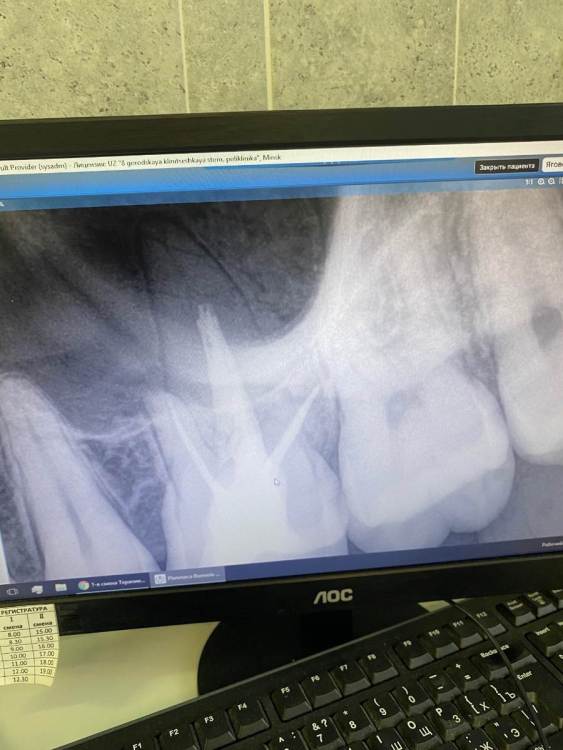

АлинаЯга Опубликовано 14 июня, 2022 Поделиться Опубликовано 14 июня, 2022 Здравствуйте . Полгода назад удаляли нервы . через месяц перелечивали ,так как канал был плохо запломбирован . Сейчас зуб начал реагировать на горячее и болеть при постукивании . Сделала снимок . что скажите ? Ссылка на комментарий

red_butler Опубликовано 14 июня, 2022 Поделиться Опубликовано 14 июня, 2022 Здравствуйте, для начало хотелось бы направить Вас на Кт. так же если есть, покажите более ранние снимки. Ссылка на комментарий

АлинаЯга Опубликовано 14 июня, 2022 Автор Поделиться Опубликовано 14 июня, 2022 @red_butler старый снимок первого лечения совсем неудачный ( Ссылка на комментарий

АлинаЯга Опубликовано 14 июня, 2022 Автор Поделиться Опубликовано 14 июня, 2022 @red_butler сделала сегодня кт . Киста такая огромная? Ссылка на комментарий

сирена Опубликовано 15 июня, 2022 Поделиться Опубликовано 15 июня, 2022 Честно, вообще не увидела разницы между снимком после первого лечения и после второго. Ищите хорошего врача для перелечивания. Ссылка на комментарий